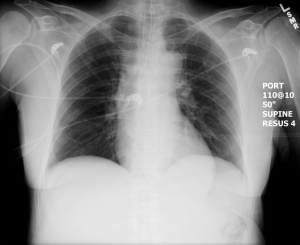

CXR for case found here:

(CXR source: https://emcow.files.wordpress.com/2012/11/normal-intubation2.jpg)